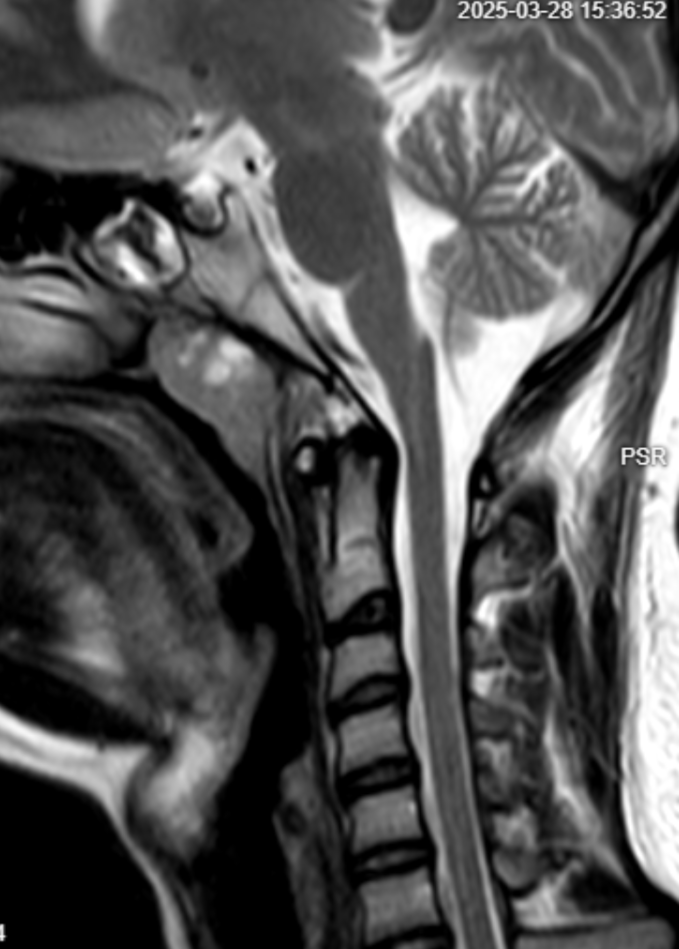

MRI Scan Analysis CT Scan Analysis Temporal Scan Analysis Orbits Scan Analysis MRI Scan Analysis CT Scan Analysis Temporal Scan Analysis Orbits Scan Analysis

Primary Reads & Second Opinions

We do primary reads and second opinions. For collaborating or partnering for primary reads of scans, please connect with us at reach@hnnradiologist.com.

MRI Brain / Spine: ₹1000